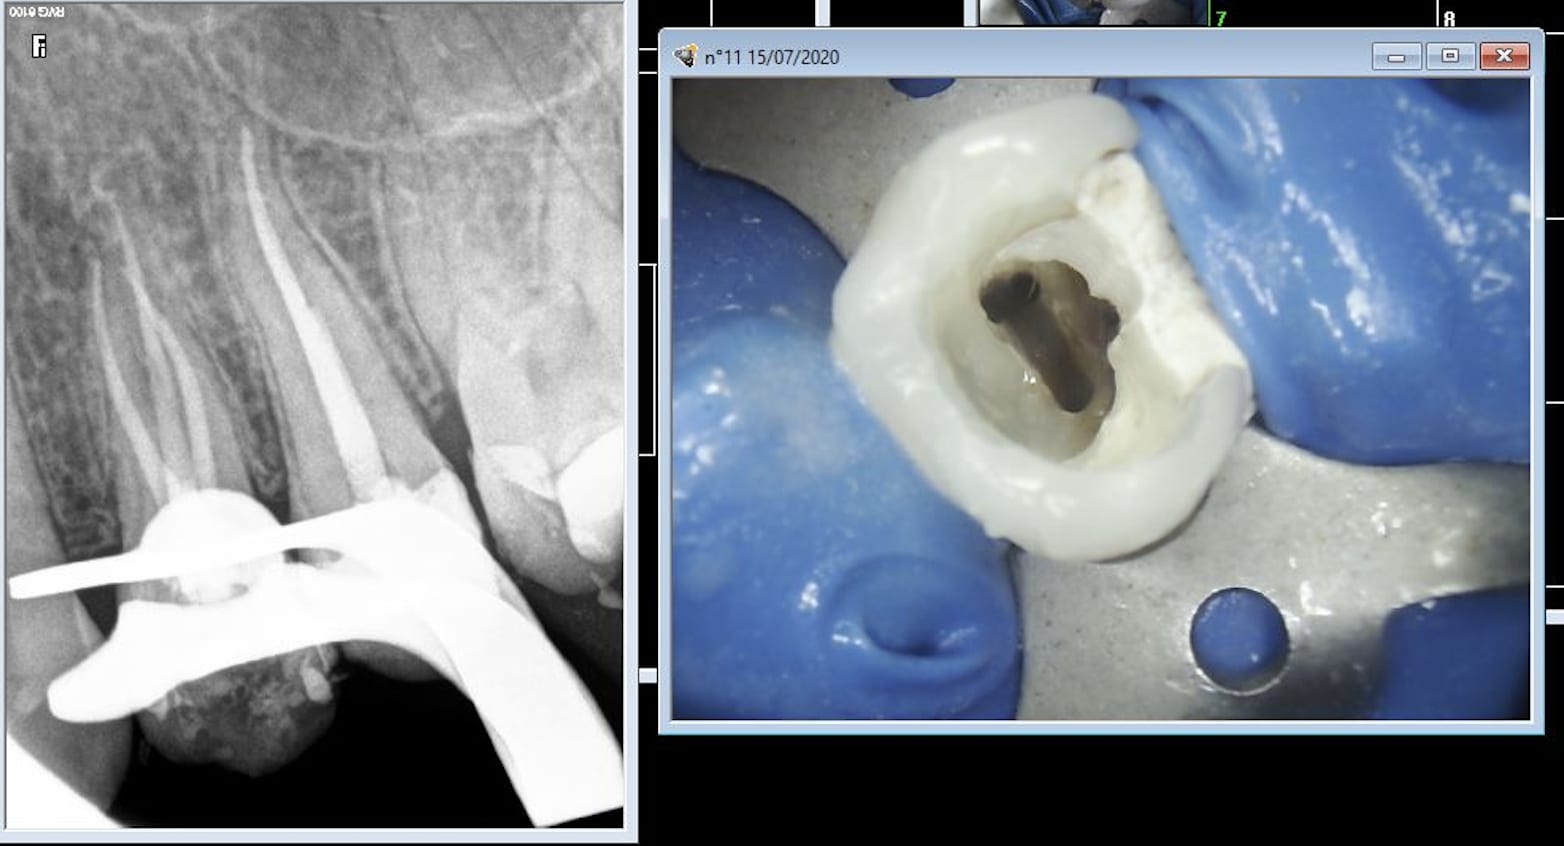

Comparaison des traitements de 2 praticiens différents au même tarif. Même patient 16 26. Pourquoi se faire chier aucun souci sur 26. ,

> Comparaison des traitements de 2 praticiens différents au même tarif. Même

> patient 16 26. Pourquoi se faire chier aucun souci sur 26. ,

c est terrible parce que selon Gabzou... le gars qui a foiré l endo 26 a fait exprès puisque c est facile...

si c était si facile, tout le monde le ferait.

> c est terrible parce que selon Gabzou... le gars qui a foiré l endo 26 a fait

> exprès puisque c est facile...

> si c était si facile, tout le monde le ferait.

Il y a un nouveau concept : c'est pas que ce soit facile c'est qu'il s'en foutent. Tu me diras au tarif sécu rien d'étonnant. Vas trouver une assistante ou n'importe quel salarié qui va faire consciencieusement des heures sup non payées parce qu'elle le vaut bien. je prends une heure 30 par molaire et 1H pour les autres endos ( avec reconstitution ) contre 1H et 30 mn avant. Bien sur j'arrive à le faire en moins de temps la plupart du temps mais si je ne prends pas le temps qu'il faut, ce boulot que tu apprends à aimer ( c'est pas inné au départ ) se transforme en corvée. Un autre nouveau concept élaboré aussi par un de nos confrères, salarié du contrôle dentaire, c'est que la justification du tarif indigent des endos est que on se "rattrape" sur la couronne qui va dessus, de là à penser qu'on dévitalise pour faire des couronnes il n'y a qu'un pas qui est franchi allègrement par certains . Du coup je me mets à faire des couronnes sur dents vivantes ce que je ne faisais jamais avant , on fait une endo parce qu'on a peur qu'il y ait des sensibilités ou une nécrose après pas pour poser l'indication d'une couronne pour délabrer une dent qui l'est déjà. Une endo facile c'est comme une extraction facile a priori ca n'existe pas tu peux dire que c'est facile ou difficile une fois que tu l'as faite. Le plus souvent c'est facile.

rien a redire sur les endos de chicot

neanmoins la question de gabzou concernant le % de cas réellement difficiles est intéressante car chicot tu illustres ce propos par des cas que tu dois trouver emblématiques datant de 2019/2020

Indépendamment du reste, il y a clairement une racine MV non traitée dont on distingue le canal, ce qui est l'anatomie standard d'une 26.

Conclusion, le praticien l'a sciemment ignorée pour aller plus vite.

On peut discuter de la rémunération, des raisons qui ont amené ce praticien à choisir de bâcler le travail, mais il est indiscutable que le praticien ne peut pas avoir ignoré avoir fait n'importe quoi.

J'ai bien précisé que tout n'est pas facile. Cette 26 l'est, je n'ai quasiment aucun doute.